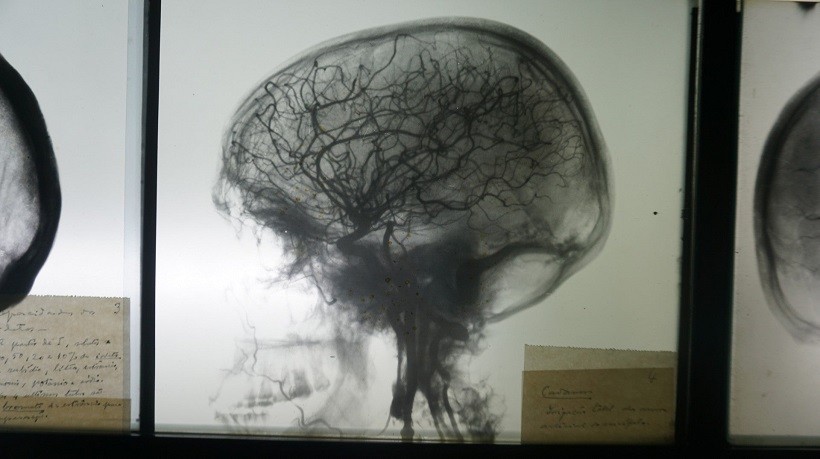

O encontro europeu “é mais uma prova dessa vitalidade relacional entre o Município/ Direção da Casa Museu Egas Moniz e a promoção da Educação, História e Ciência, com a cedência temporária de material expositivo histórico-científico, assim como de natureza documental a todos os congressistas, ressalvando-se ainda a iniciativa conducente à presença, no evento, da icónica “mesa da angiografia”, onde Egas Moniz realizou a 1ª Angiografia Cerebral de sempre (28 de Junho, 1927) e que lhe valeria, mais tarde, o Prémio de Oslo e o catapultaria indubitavelmente na marcha para o Prémio Nobel.

Para a Diretora da Casa Museu Egas Moniz, Rosa Maria Rodrigues, estar presente neste congresso significa “o consolidar da parceria, do Município de Estarreja com a Sociedade Portuguesa e Neurorradiologia e outras agremiações científicas, bem como, vivificar a vida e a obra do Neurocientista Egas Moniz que, indubitavelmente, deve ser inserido na História da Medicina do século XX, pela persistência e tenacidade com que desbravou o desconhecido, notoriamente com a Angiografia que é uma das temáticas base deste Congresso.”